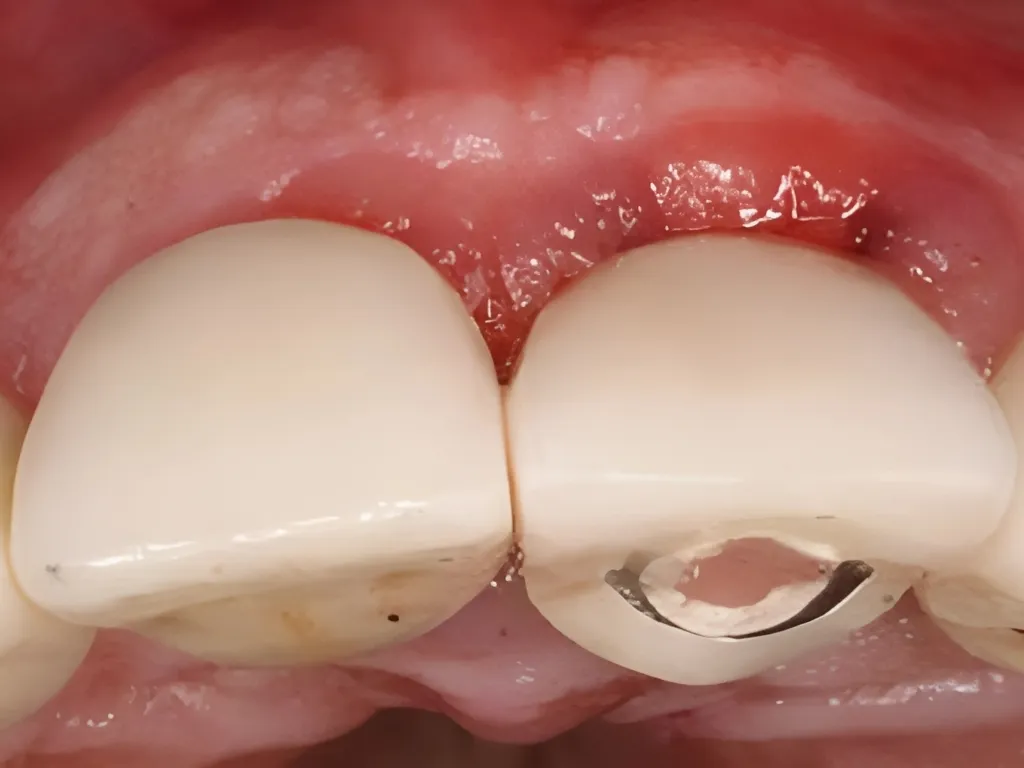

vaka_img

Soket Koruma ve Immediate Yükleme

Dr. Manuel de la Rosa & Dr. Roberto Anzaldua